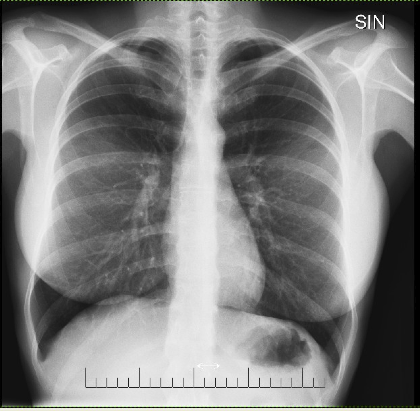

35 year old female.

8 months of chest pain, breathing difficulties, new onset asthma and allergies. Low grade fever. One month of severe itch and rashes. Numbness, eye problem, general weakness and abdominal, back and pelvic pain. Foreign body feeling in upper body. Sudden dizziness and nausea. Weight loss. Fluctuating blood pressure. Increased pulse pressure. Memory problem and fatigue. Muscle spams. Excessive hair loss. Feeling of neck tightness.

PIP breast implant 10 years ago.

Chest X-ray taken 5 months earlier